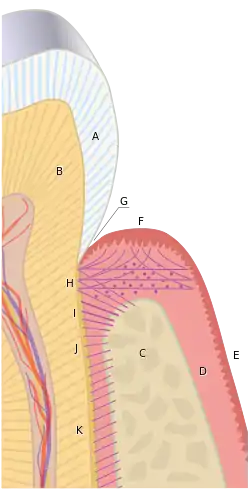

Crown and root

The term "crown" of a tooth can be used in two ways. The term "anatomic crown" of a tooth refers to the area above the cementoenamel junction (CEJ) or "neck" of the tooth.[9] It is completely covered in enamel. The term "clinical crown" often is convenient in referring to any part of the tooth visible in the mouth, but as a rule the unqualified term "crown" refers to the anatomic crown. The bulk of the crown is composed of dentine, with the pulp chamber within. The crown is enclosed within bone before the tooth erupts, but after eruption the crown is almost always visible in an anatomically normal and clinically healthy mouth.

The anatomic root is found below the cementoenamel junction and is covered with cementum, whereas the clinical root is any part of a tooth not visible in the mouth. Similarly, the anatomic root is assumed in most circumstances. Dentin composes most of the root, which normally has pulp canals. The roots of teeth may be single in number (single-rooted teeth) or multiple. Canines and most premolars, except for maxillary first premolars, usually have one root. Maxillary first premolars and mandibular molars usually have two roots. Maxillary molars usually have three roots. The tooth is supported in bone by an attachment apparatus, known as the periodontium, which interacts with the root.

The enamel organ is composed of the outer enamel epithelium, inner enamel epithelium, stellate reticulum and stratum intermedium.[3] These cells give rise to ameloblasts, which produce enamel and the reduced enamel epithelium. The growth of cervical loop cells into the deeper tissues forms Hertwig's Epithelial Root Sheath, which determines the root shape of the tooth. The dental papilla contains cells that develop into odontoblasts, which are dentin-forming cells.[3] Additionally, the junction between the dental papilla and inner enamel epithelium determines the crown shape of a tooth.[2] The dental follicle gives rise to three important entities: cementoblasts, osteoblasts, and fibroblasts. Cementoblasts form the cementum of a tooth. Osteoblasts give rise to the alveolar bone around the roots of teeth. Fibroblasts develop the periodontal ligaments which connect teeth to the alveolar bone through cementum.[4]